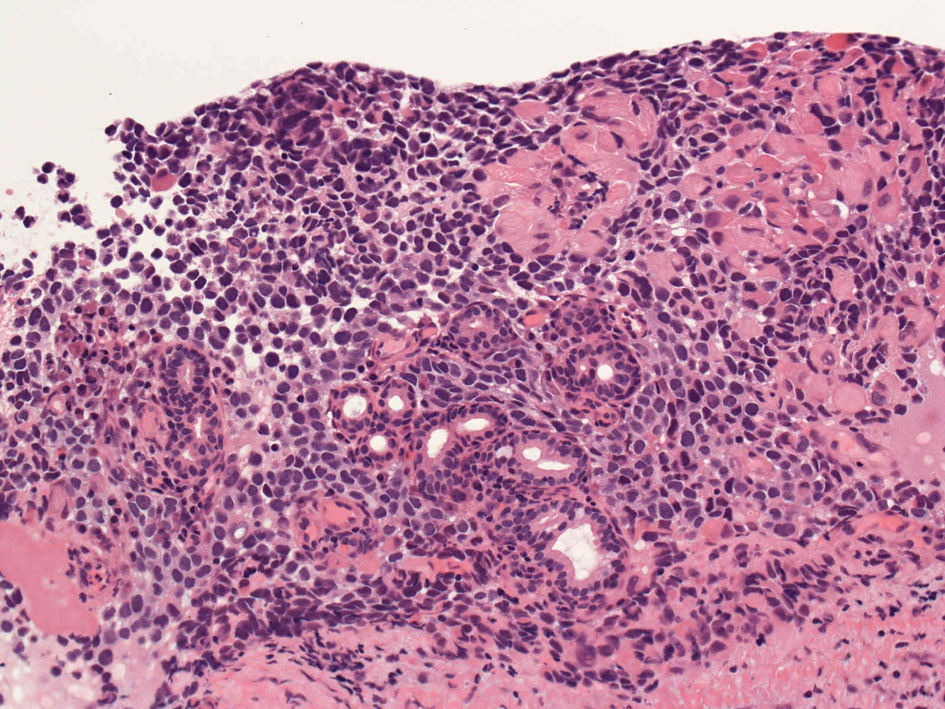

40歳女性 鼻粘膜腫瘤

右頸部のしこりを自覚。近医MRIで頸部多発リンパ節腫大あり当院を紹介される。右顎下, 右鎖骨上窩にも多数のリンパ節を触れる。穿刺細胞診ではcarcinoma疑い。右鼻腔, 上顎洞にも腫瘤が認められリンパ節腫大との関係を調べるために鼻腔腫瘤の生検が行われる。

病理組織所見

HE06.jpg